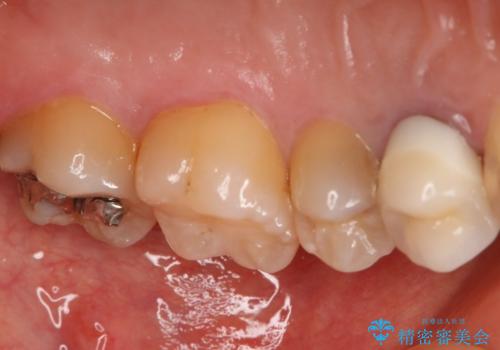

う蝕除去中に露髄 フルジルコニアクラウン

う蝕が神経近接にまで達していたので露髄する可能性を説明しました。

その場合、精密根管治療・クラウンになることもお伝えしています。

う蝕除去中に露髄したため精密根管治療へと切り替え、仮歯をはさんでセラミッククラウンを装着し終了としました。

*根管治療は保険を希望されました。